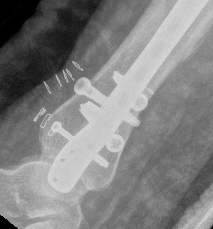

Intra-medullary Nail

Indications

- wounds / soft tissues not suitable to plate

- relatively stable

- sufficient distal bone

Design

Distal tibial nails

- multiple distal screws

- usually 2 medial-lateral and 1 AP

- most distal screw within 5 mm of end of nail

Technique

Consider semi-extended suprapatella nail

- easier to reduce fracture

- easier to get AP and lateral fluoroscopy

Most important is to centre guide wire over talus

- in lateral and AP

- use finger reduction tools and pass across fracture site to exact centre in AP and lateral

- bone reduction forceps

- blocking screws

- universal external fixation

- plate fibula

Fibular fixation

Peng et al. J Foot Ankle Surg 2021

- tibial IMN +/- fibular fixation

- meta-analysis of 4 trials, 283 patients

- tibial malalignment of 67% (126 / 189) in non fibular fixation group

- tibial malalignment of 20% (19/94) in the fibular fixation group

https://pubmed.ncbi.nlm.nih.gov/33218862/